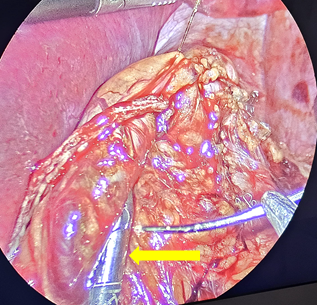

The SG is then performed by dividing the gastroepiploic omentum from the greater curvature with an ultrasonic scalpel (Sonicision TM Medtronic) starting 6cm from the pyloric vein to the angle of His, until the left crura of the hiatus was observed. The gastro-splenic and gastro-phrenic ligaments are also divided. The fat pad that covers the His angle is excised with the same instrument. A 36Fr bougie is passed to the stomach to construct the gastric tube using five or six cartridges of the Endo GIA 60 tristaple (CovidienTM) to divide the greater curvature. The proximal gastric plication is then performed to create an internal antireflux valve in the upper 3cm on the lateral side of the gastric tube by using a grasper to invaginate 2cm of the gastric wall of the stomach with sero-muscular stitches of a running suture of 2-0, 45cm spiral Monocryl (Stratafix Ethicon ®), and then continue the suture to reinforce the rest of the staple line (Figure 1-3). This invagination reduces the gastric bulb that is frequently observed at the proximal staple line and serves to decrease the gastric lumen at this point; serving as an internal anti-reflux valve.

Figure 1 Start of the running suture with 2-0 spiral Monocryl